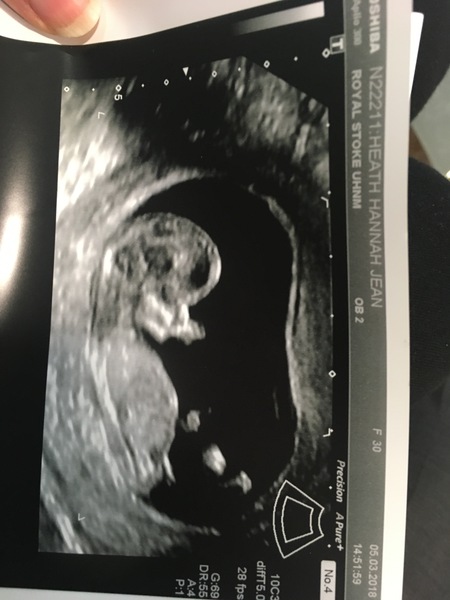

HannahJH · 05/03/2018 16:13

Please may I be added to the FB group? Due 19/9? X

Beautiful scans Hannah and Mummy

@HannahJH I've added you to the group it's just pending admin approval.... x